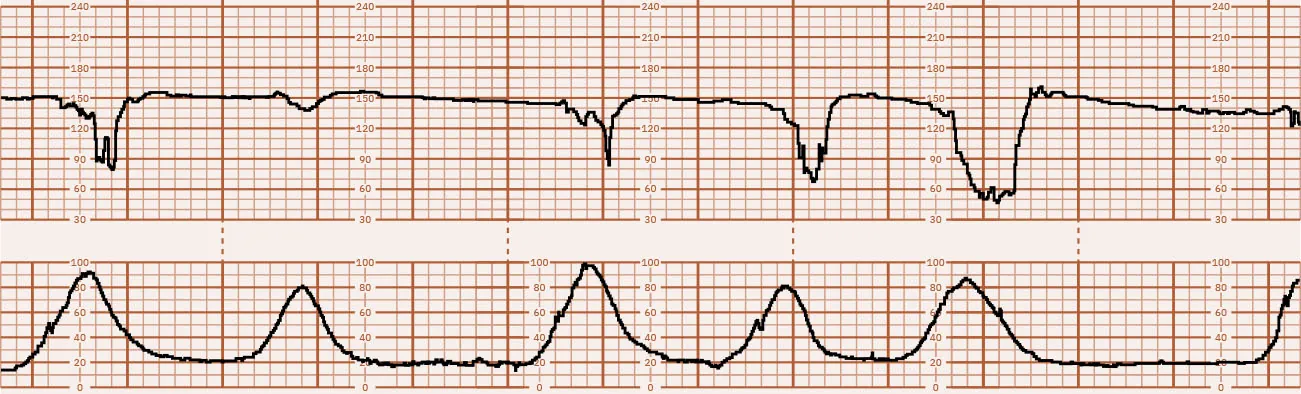

Category I tracings are considered normal and do not require further actions by the nurse other than routine nursing care for the antepartum or laboring patient. Figure 16.26 shows a Category I tracing. Category II tracing characteristics do not meet the criteria of either Category I or III. Nursing care requires continued surveillance with consideration of clinical circumstances and reevaluation and notification of the health-care provider. Figure 16.27 shows a Category II tracing. Category III tracings are always considered abnormal and require the nurse to contact the health-care provider with a report of the FHR abnormalities. Nursing interventions aimed at resolving the cause of the abnormality are discussed in 16.5 Intrauterine Resuscitation in this chapter. If interventions do not resolve the abnormality, the birth must be expedited, most commonly via cesarean section (ACOG, 2009). Figure 16.28 shows a Category III tracing.

Fetal heart rate reading showing minimal variability.

Figure 16.27 Category II Tracing This fetal heart rate tracing shows minimal variability. (attribution: Copyright Rice University, OpenStax, under CC BY 4.0 license)